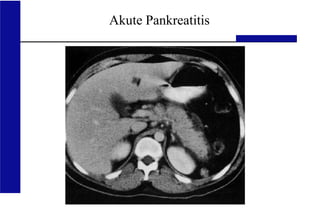

Akute Pankreatitis

normales Pankreas akute nekrotisierende

Pankreatitis